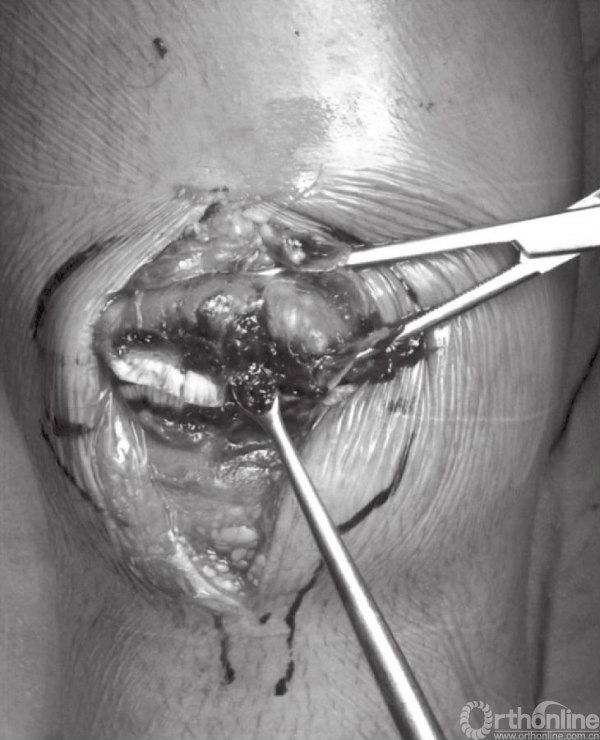

骨折末端应以小挂勺以及吸引器清除局部的血凝块。骨折端处的骨膜以及韧带应分离至骨折线周围2~3cm处,以免影响骨折复位。但应注意,不要清除髌骨周围过多的软组织,因为常有骨折块包含其中。

应仔细探查关节,以辨识游离骨块以及关节面损伤(图6)。此时,可对骨折进行复位,并以复位钳进行临时固定。检查骨折复位情况以及关节稳定性,关节内骨块的解剖复位是非常重要的。术中复位困难,可能是因为小骨块或者软组织嵌于骨折端。